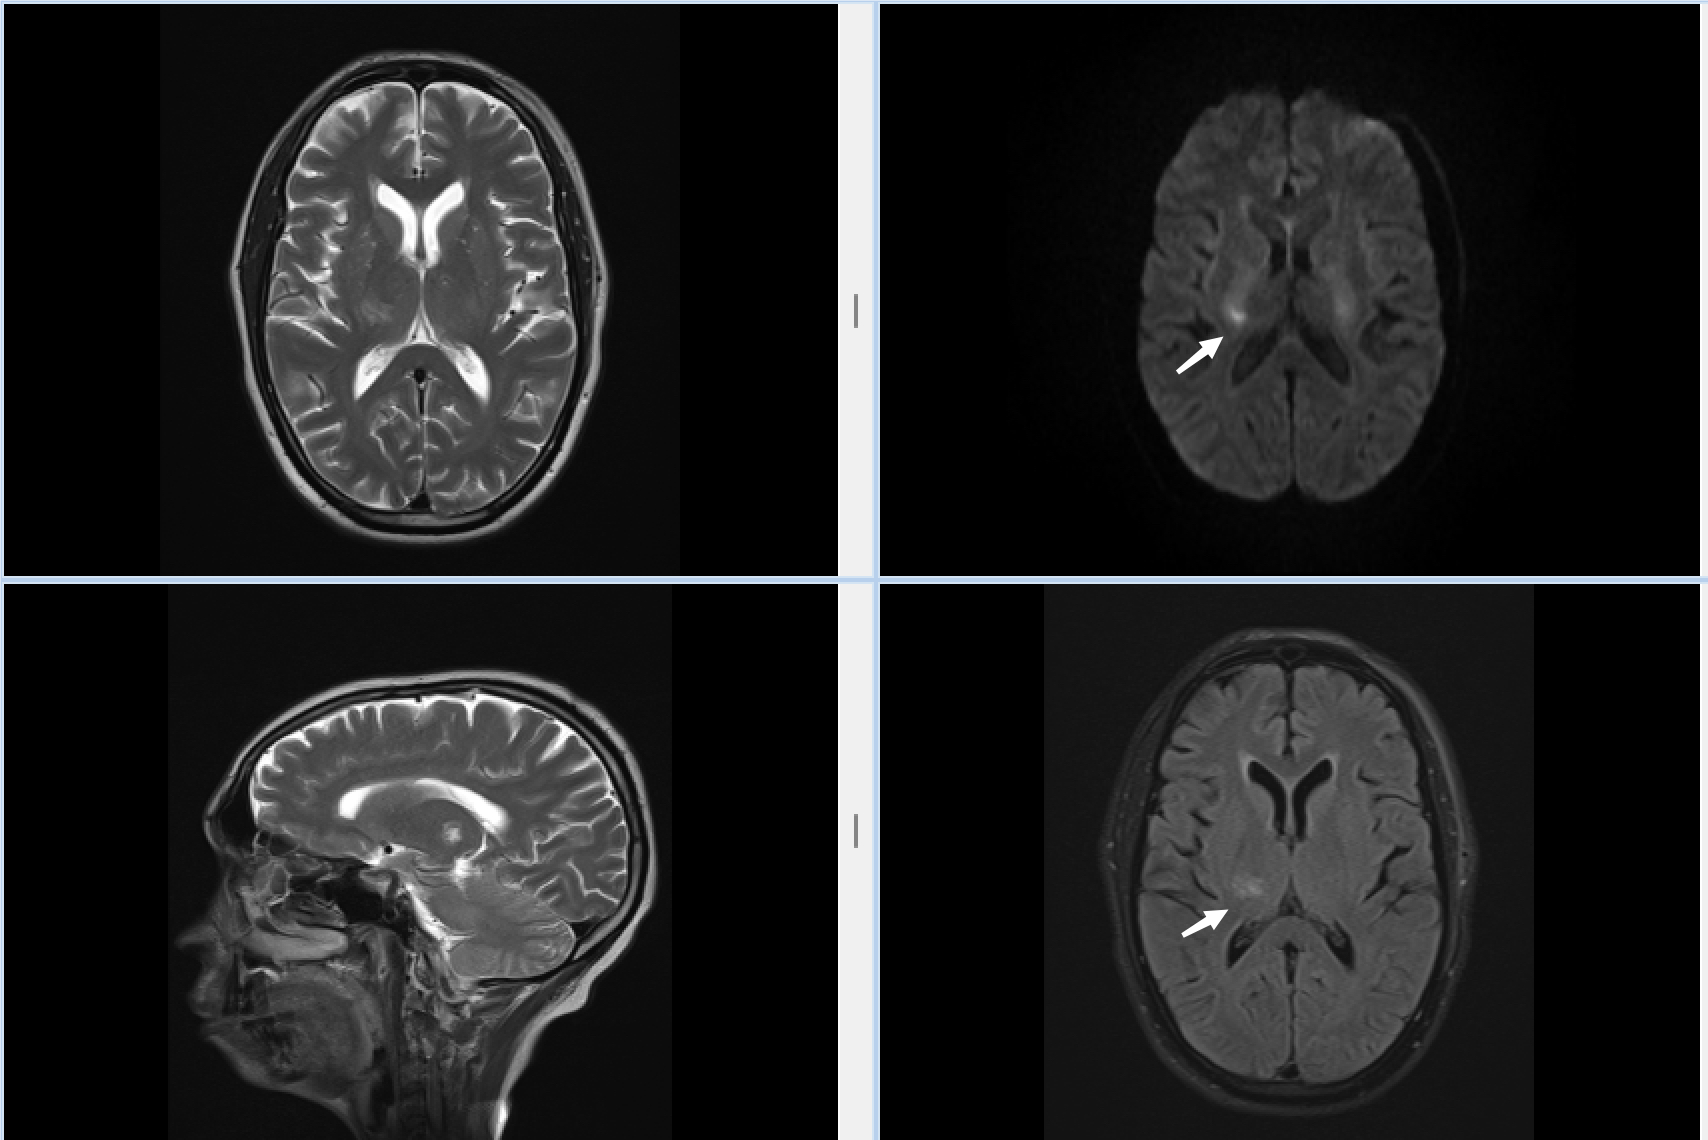

此次接受检查的首位患者,因“左侧肢体偏瘫、麻木伴深感觉障碍1日”就诊。患者此前接受头颅CT检查未发现明显异常,病情诊断陷入困境。为精准明确病因,耿磊副主任医师团队果断启用新落地的磁共振设备,通过头颅常规扫描及功能成像分析,清晰显示患者右侧丘脑存在急性梗死灶,为临床制定诊疗方案提供了确凿依据。这一诊断结果也印证了磁共振在早期脑血管疾病诊断中的独特优势,有效避免了因漏诊导致的治疗延误。

磁共振检查的成功落地,为奔巴岛神经系统疾病诊疗带来质的飞跃。相较于传统CT检查,磁共振在软组织分辨力、早期病变识别等方面具有显著优势,尤其对脑梗死、脑肿瘤、脑血管畸形等疾病的诊断准确率更高。此次首例诊断案例,正是凭借磁共振的精准成像,成功捕捉到CT未能显示的早期丘脑梗死灶,为患者赢得了黄金治疗时间。耿磊副主任医师介绍,丘脑作为人体感觉传导的“中枢枢纽”,急性梗死若未能及时确诊治疗,极易导致肢体感觉障碍加重、偏瘫程度恶化等后遗症,磁共振技术的应用将大幅提升当地此类疾病的诊疗效率与效果。